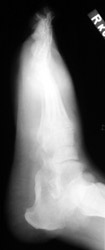

Gout: AP- Erosions 1st MTP joint with tophiGout: AP- Erosions 1st MTP joint with tophiTophaceus Gout: LateralTophaceus Gout: APGOUT is caused by monosodium urate or uric acid crystal deposition within cartilage, bone, or periarticular tissues.

First metatarsophalangeal joint is most commonly affected, followed by the first interphalangeal joint and tarsometatarsal joints. Posterior calcaneal involvement has also been noted. The majority of first presentations are monoarticular. Bilateral and symmetric or asymmetric polyarticular involvement may be present within any of the foot joints.

Acute, episodic soft tissue swelling may represent the earliest radiographic sign. Later, sharp, round or oval marginal joint erosions with sclerotic borders are classically seen with gout. These findings most commonly occur along the dorsum of the foot. Associated soft tissue tophi or intraosseous nodules may be present. "Overhanging margin" occur where the bone resorbs beneath a tophaceous nodule. Joint spaces are usually preserved, but ankylosis may rarely occur with advanced stages of gout. The aforementioned findings may be in different stages of progression with any given patient.